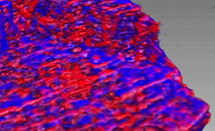

Osteoarthritis (OA) is a debilitating disease and worldwide healthcare burden. It is characterised by the loss of articular cartilage that normally covers the ends of bones to allow pain free movement. Current clinical strategies only manage the joint pain and do not address the underlying molecular mechanisms that trigger and fuel this degenerative disease. Prior studies have suggested that cells in the articular cartilage undergo uncharacteristic changes, which may result in the deterioration of this tissue. However, little is known of the involvement of a further type of cartilage critical for bone lengthening, known as growth plate cartilage. Read More

Osteoarthritis (OA) is a debilitating disease and worldwide healthcare burden. It is characterised by the loss of articular cartilage that normally covers the ends of bones to allow pain free movement. Current clinical strategies only manage the joint pain and do not address the underlying molecular mechanisms that trigger and fuel this degenerative disease. Prior studies have suggested that cells in the articular cartilage undergo uncharacteristic changes, which may result in the deterioration of this tissue. However, little is known of the involvement of a further type of cartilage critical for bone lengthening, known as growth plate cartilage. Read More

I13 is partly operated in collaboration with the University of Manchester. The collaboration has been running since 2010 and gives the university speedy and streamlined access to Diamond’s imaging and tomography capabilities. Scans capture 3D images using partially coherent radiation which enables contrast enhancement at the edges of structures. This ‘in-line phase contrast imaging’ is particularly useful for biomedical applications where the contrast between structures is weak. Imaging of soft tissue is now possible and 2015 saw a remarkable study of a mouse knee, with the bone, cartilage and other soft tissue distinguishable. The study, by Professor Andrew Pitsillides of the Royal Veterinary College, University of London, looked at the knee joints of mice, genetically engineered osteoarthritis1. Using microtomography they were able to quantify the abnormal bone growth in the joints.